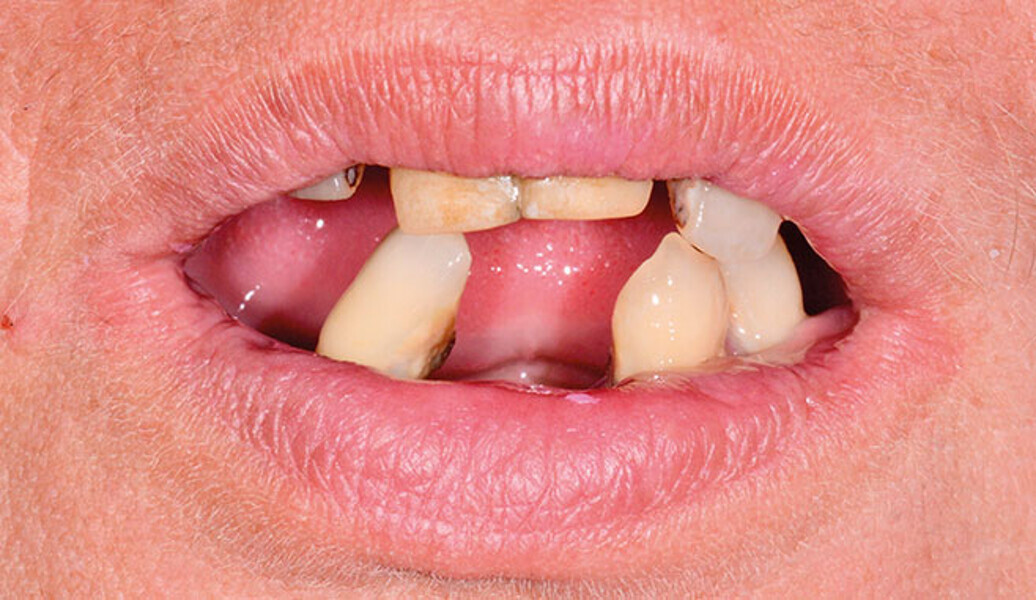

Protocollo SKY fast & fixed